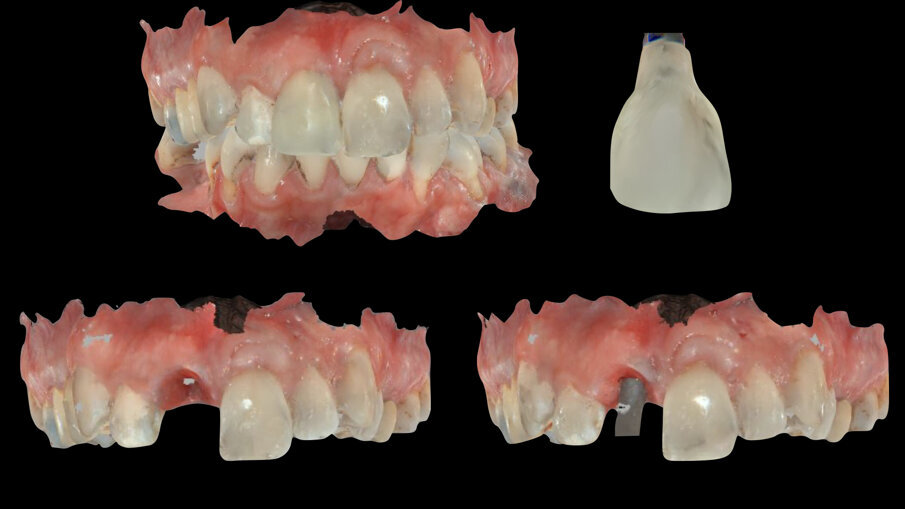

L’esame CBCT è stato integrato con impronte digitali delle due arcate tramite scanner ottico Carestream 3600 (Carestream Dental Rochester New York Stati Uniti) e i file Dicom ed STL e la ceratura diagnostica digitale sono stati caricati in un software di programmazione chirurgica (3 Diemme srl Como) dove è stato progettato il posizionamento dell’impianto sull’1.1, impianto Imax 3.3 x 13 (Ires Group Mendrisio [CH]), da inserire tramite chirurgia guidata con dima chirurgica ad appoggio dentale5.

La finalizzazione del caso ha previsto l’utilizzo di un protocollo di scansione digitale con impronta ottica dell’arcata dentaria con provvisorio in situ, del provvisorio fuori della bocca, del condizionamento dei tessuti molli (tragitto transmucoso) e della posizione implantare rilevata con lo scan body, oltre naturalmente all’impronta antagonista e il check di registrazione occlusale9 (Fig. 18): tutto ciò permette di leggere il condizionamento dei tessuti molli ottenuti e il profilo del provvisorio (corretto nella fase di guarigione) che l’ha determinato e ricreare una corona definitiva che si “appoggi” perfettamente nei tessuti così ottenuti.